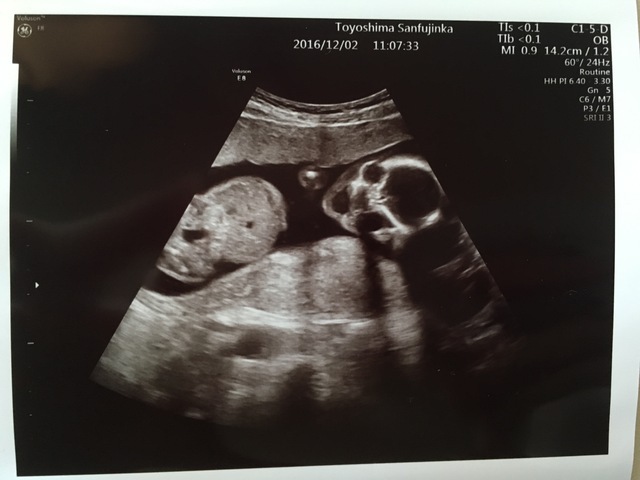

18週3日(18w3d・女の子)|よーちゃん、! さん(27歳)

エコー写真撮影時のエピソード:

妊娠7ヶ月のプレママです。

妊娠6ヶ月に入るまで、私は胎動を全く感じませんでした。

このエコー写真の時期はもちろん胎動がなく、赤ちゃんが無事に生きているのかとても心配でした。

そんな時エコー写真で赤ちゃんの背骨をはっきり見ることができて、大きくなってきているのだなあととても嬉しくなりました。

赤ちゃんってだんだんと人間らしくなっていくのですね。

パパにエコー写真を見せた時、これが背骨だよっと教えると、すごいなあーとびっくりしていました。

産まれるまであと3ヶ月です。

赤ちゃんに会えるのが楽しみです。